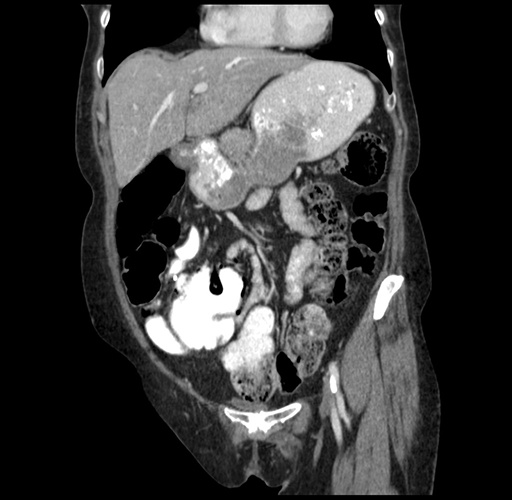

Coronal Venous